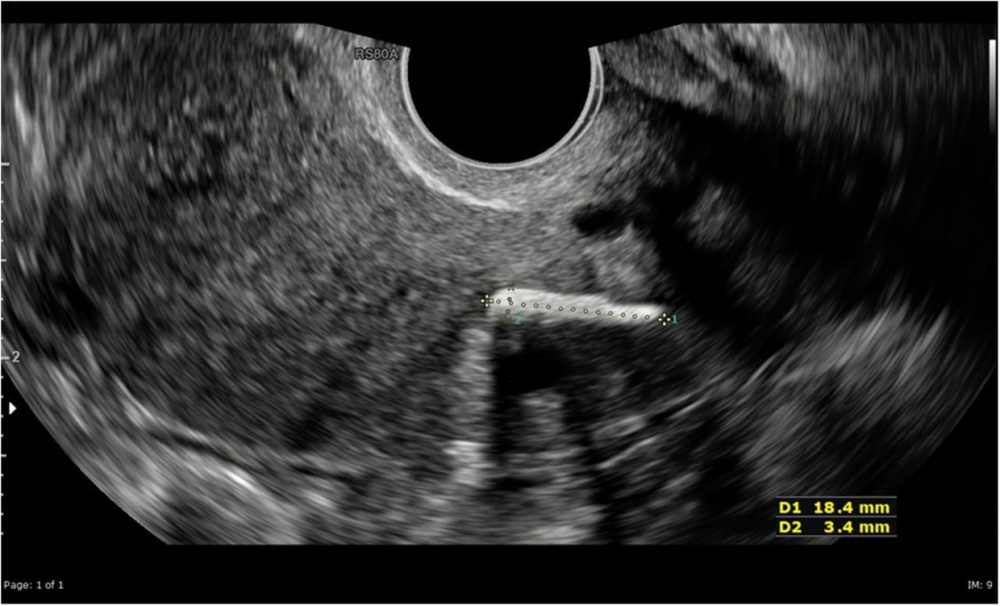

不過該女子和丈夫過去曾是煙民,因此被診所要求戒煙後一年再進行生育治療評估。一年後,女子如期到診所覆診,但卻訴說自己左下腹部出現明顯的慢性疼痛,嚴重的經痛更是折磨著她。醫生察覺不妙,馬上為女子進行超聲波檢查,看看是否罹患多囊性卵巢症(PCOS)或是輸卵管阻塞等疾病,然而他們始終無法發現導致疼痛的異常。最後,在進行腹腔鏡檢查和著色試驗時,醫護人員終於在女子的子宮頸組織中發現一小塊幾毫米長的條狀異物。

異物被取出化驗後,證實是一片嬰兒骨頭碎片,才知曉原來女子在20年前曾經進行流產手術,相信是當時胚胎組織未被完全清除乾淨所致。醫生表示,胚胎殘骸可導致月經不調,甚至不孕症,也有可能導致其他併發症,不可忽視。然而由於碎片不大,醫生相信這也是過去超聲波及CT檢查無法檢測出的原因,造成女子一直被誤診,而女子此後能否順利懷孕依舊未知。